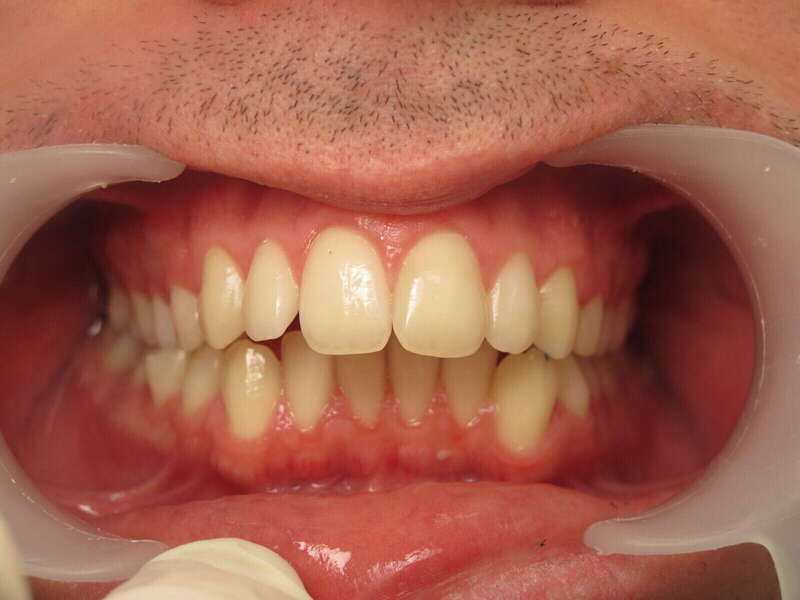

L'examen initial révélait une situation complexe nécessitant une action sur l'alignement et sur l'emboîtement des mâchoires :

• Encombrement bimaxillaire : Un manque de place important aux deux arcades (supérieure et inférieure), entraînant des chevauchements dentaires et des rotations gênant à la fois l'esthétique et l'hygiène.

• Prognathie dentaire inférieure : Les dents du bas se situent trop en avant par rapport aux dents du haut. Sans correction, ce décalage empêche un engrènement stable et peut fragiliser le parodonte des incisives.

• Sourire irrégulier : L'alignement défaillant brisait l'harmonie du sourire, avec des dents situées hors de la courbe idéale.

Éléments clés du résultat (Photos "Après")

La réussite de ce traitement a reposé sur une mécanique de précision et, surtout, sur une coopération sans faille de la patiente :

1. Alignement et Nivellement : L'utilisation de bagues a permis de redresser chaque dent et de créer des arcades aux courbes fluides et régulières.

2. Gestion de l'Ancrage par Élastiques : Le port rigoureux d'élastiques intermaxillaires (entre le haut et le bas) a été l'élément moteur pour reculer le bloc inférieur et avancer légèrement le bloc supérieur.

3. Obtention d'une Classe I Canine et Molaire : Le résultat final montre un engrènement "en clé", où les dents s'emboîtent parfaitement, assurant la stabilité du traitement.

4. Harmonisation faciale : Le profil et le sourire sont désormais équilibrés, avec un soutien labial optimal.

Effets positifs du traitement pour la santé de la patiente

• Pérennité du Parodonte : En replaçant les dents du bas correctement par rapport au haut, on supprime les traumatismes occlusaux qui peuvent causer des déchaussements prématurés.

• Facilité d'Entretien : Des dents parfaitement alignées permettent un brossage efficace, réduisant drastiquement les risques de caries et de gingivites.

• Protection Articulaire : Un bon emboîtement garantit un fonctionnement sain des articulations temporo-mandibulaires (ATM), évitant les douleurs et les craquements à long terme.

• Confiance en Soi : La transformation d'un sourire encombré en un sourire aligné et harmonieux est un atout social et psychologique majeur pour une adolescente.

Légendes des photos avant/ après

• Photos "Avant" : « Encombrement sévère aux deux mâchoires avec un décalage marqué : les dents inférieures sont trop avancées, ce qui perturbe la fonction masticatoire et l'esthétique globale. »

• Photos "Après" : « Résultat final montrant un alignement parfait et un engrènement de Classe I. Ce succès est le fruit d'une excellente coopération de l'adolescente dans le port de ses élastiques de coordination. »